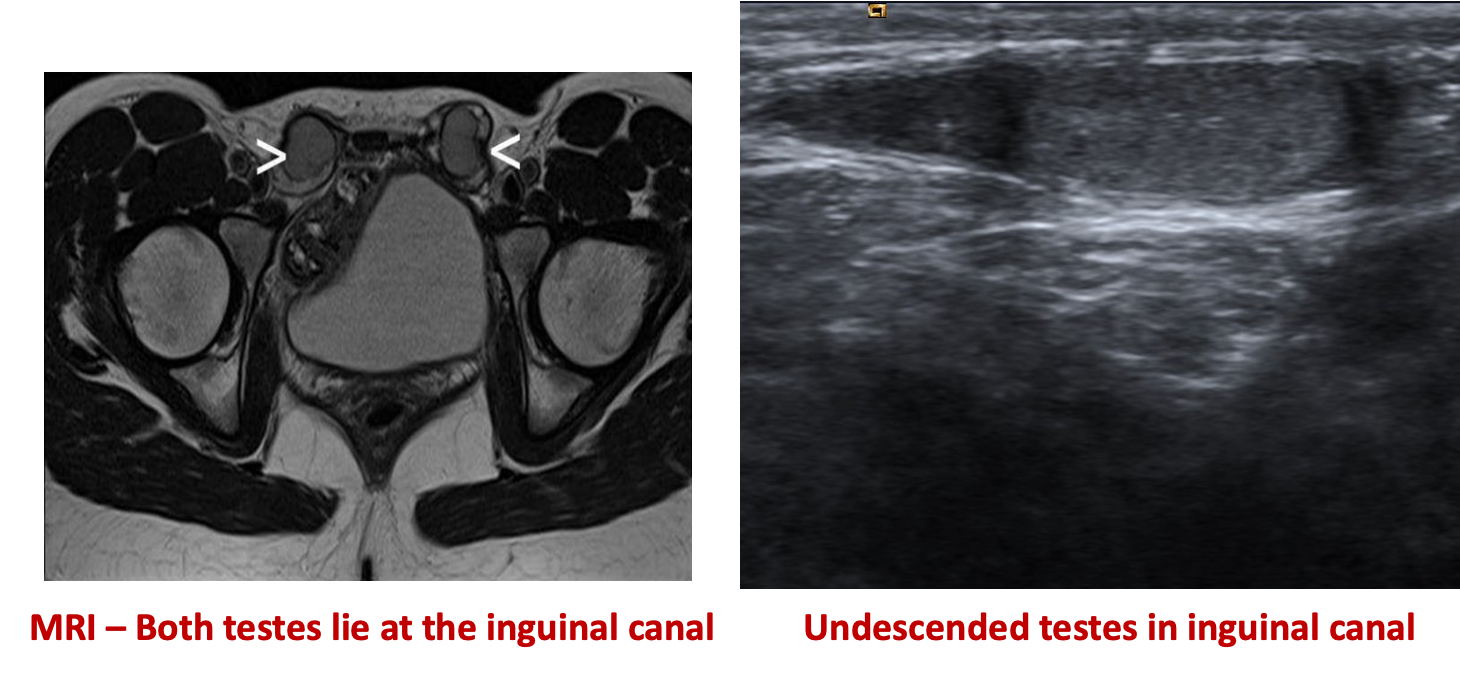

Variants Inguinal testis:

The testicle is located between the external and internal inguinal ring.

Intra-abdominal testis: testicle is located proximal to internal inguinal ring.

Testis in the inguinal canal, the commonest site, can be diagnosed by ultrasound.

Testis lies within the abdomen, or where the ultrasound is inconclusive, MRI is the investigation of choice.